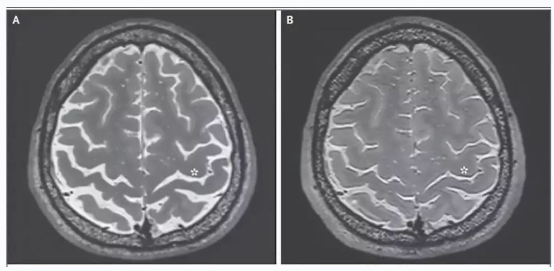

一名宇航员的大脑核磁共振成像照片,在一次长时间太空飞行前(图左)与后(图右)对比,太空飞行后,宇航员大脑中央沟变窄,脑脊液和脑蛋白质扩张。